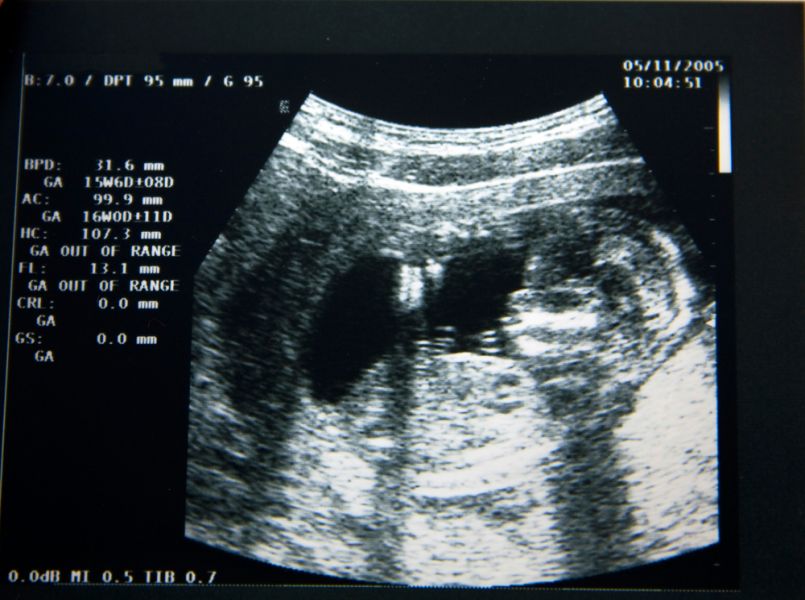

"Zo kan Eva groeien en doorgegeven worden door middel van donatie,'' schreef Keri in december op Facebook bij een foto van de echo. "Dit is het perfecte hartje van onze dochter. Ze heeft perfecte voetjes en perfecte handjes. Ze heeft perfecte nieren, longen en een perfecte lever. Helaas heeft ze geen perfecte hersenen."